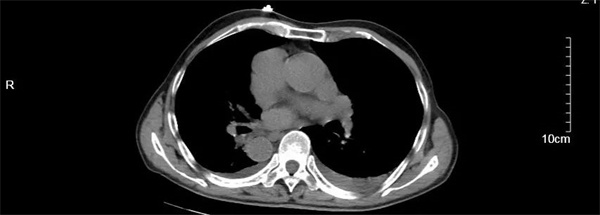

汪大爷最终被诊断为高度房室传导阻滞、镜面右位心和慢性心衰,病情十分危险。心血管内科团队评估后认为,若不及时植入心脏起搏器,汪大爷随时面临心衰加重和猝死的风险。尽管心脏起搏器植入术在池州市第二人民医院是常规手术,但为“镜面人”实施手术难度却极高。医生需要将手术习惯和技巧进行180度“转位”,这不仅要求医生有过硬的基本功和扎实的理论基础,还需对解剖结构和影像学检查熟练掌握,否则稍有不慎就会造成严重的脏器损伤。